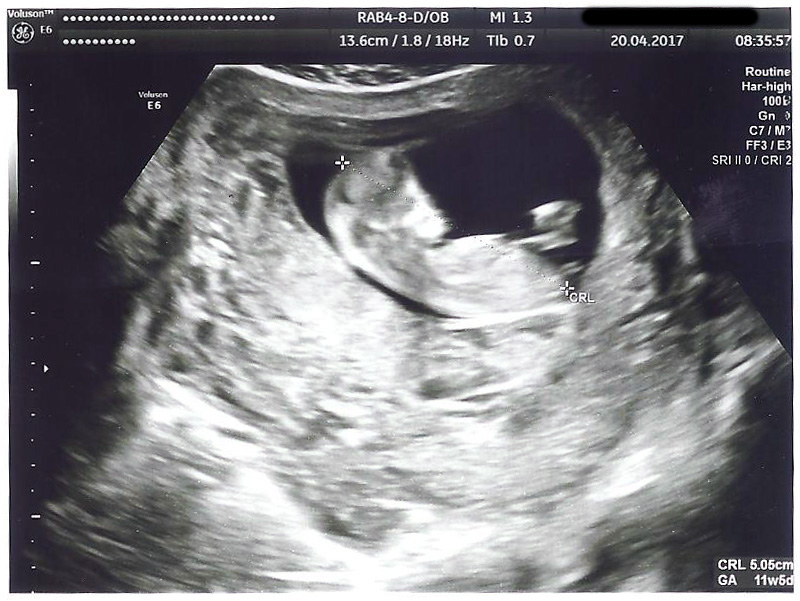

Any predictions based on Ramzi or nub theory? Thanks!

Attachment 35893

Looks like a boy to me :)

Early but boyish [emoji170]